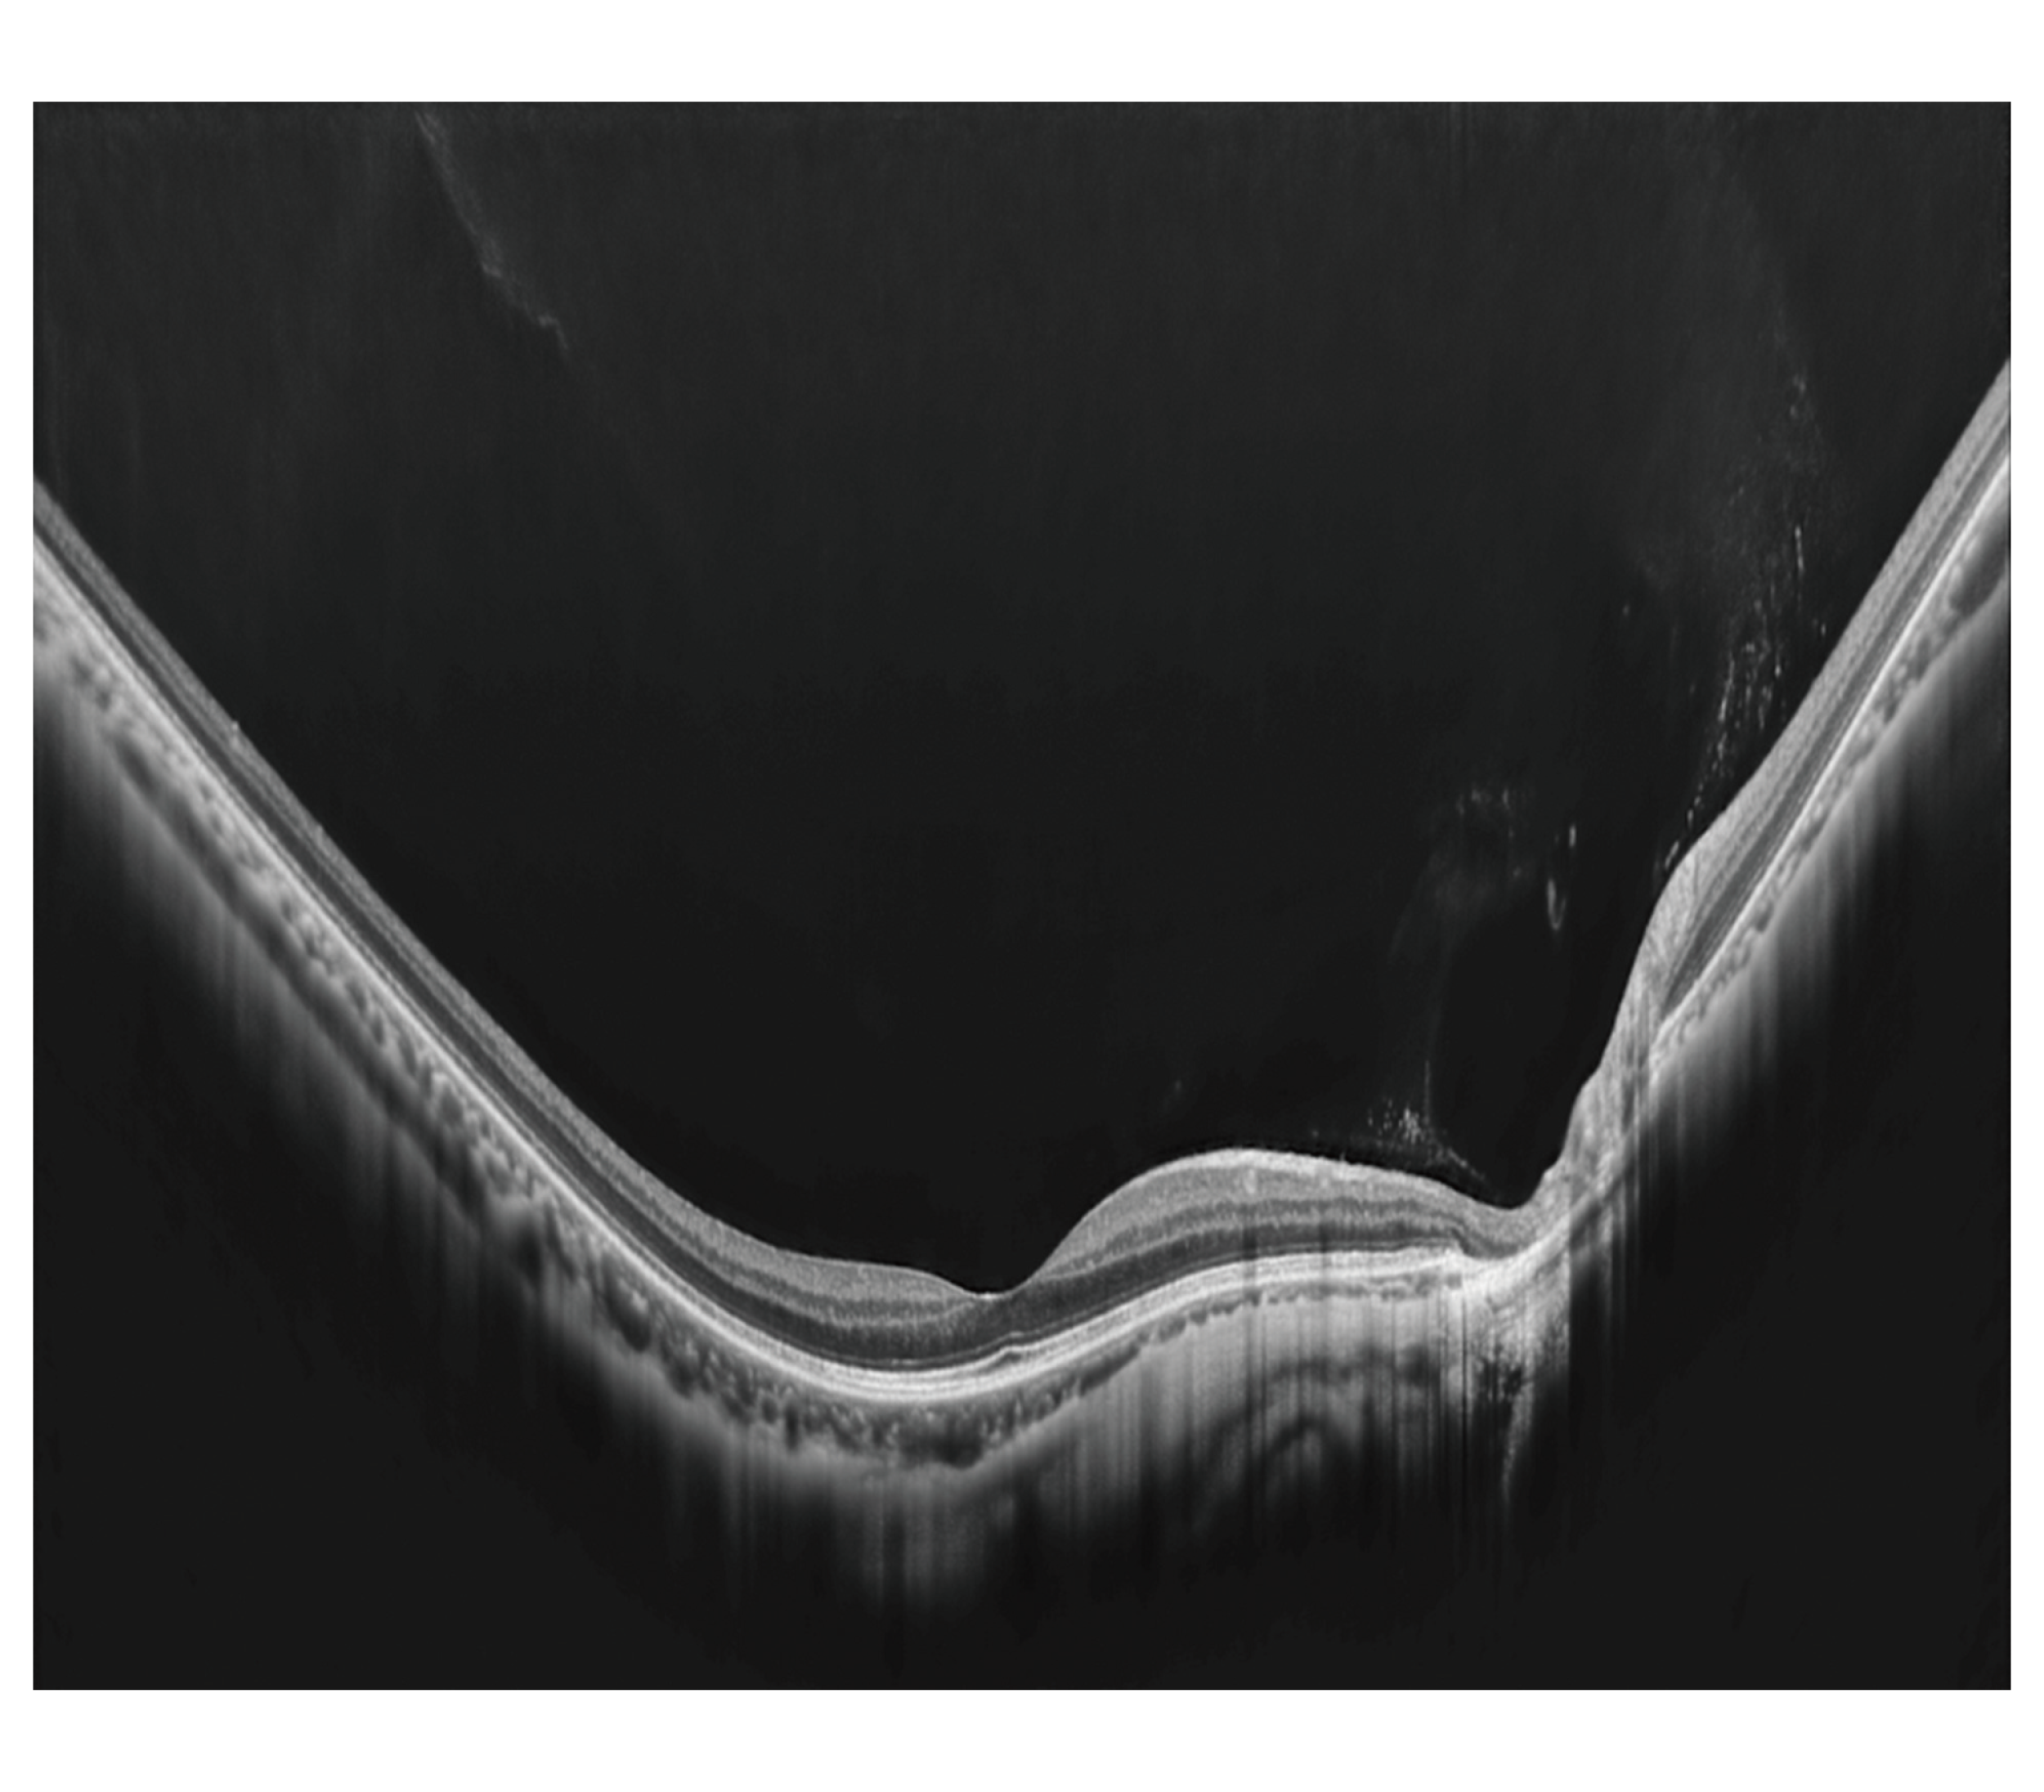

4.2mm Deep scan

従来機種*1 の2.1mmよりも深いエリアの信号をとらえることができるため、湾曲の強い眼底の撮影が容易となります。

*1 共焦点走査型ダイオードレーザ検眼鏡 Mirante、光干渉断層計 RS-3000 Advance